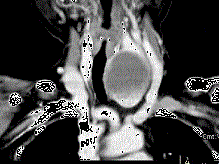

问题 女,56岁,发现颈部肿块一月余,CT如图所示,最可能诊断为 ( )

选项 A、甲状腺腺瘤 B、甲状腺脓肿 C、甲状腺乳头状癌 D、甲状腺原发淋巴瘤 E、甲状舌管囊肿

答案 A